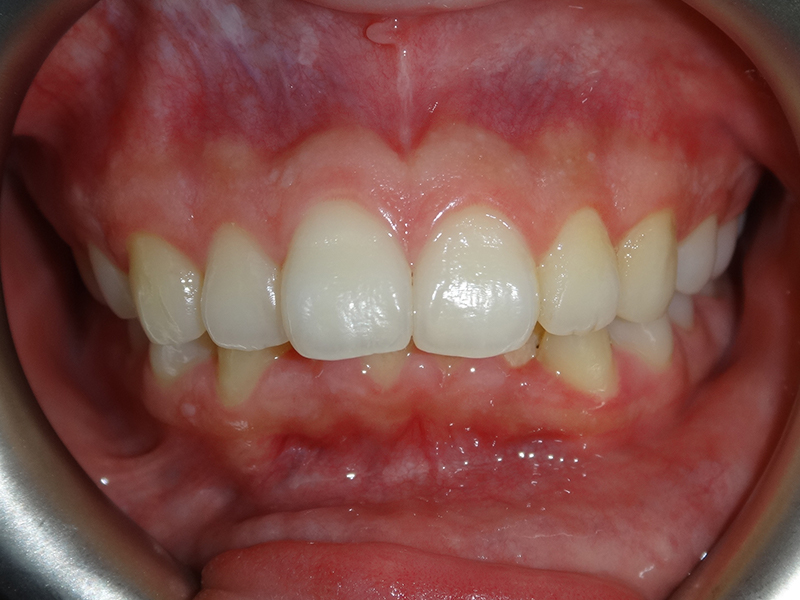

隱適美拔牙改臉型(二) 首頁 案例分享 齒顎矯正 隱適美拔牙改臉型(二) 拔牙改臉型案例 年紀:20 歲 女性 治療方式:隱適美隱形矯正 時間:29個月 主訴:外觀看起來比較暴,希望可以把牙齒排列整齊以及後縮 矯正前 矯正後 矯正前 矯正後 矯正前 矯正後 聲明:本所療程皆由專業醫生評估後,依照個人口腔狀況進行治療。因每位患者個別狀況不同,術後狀況也不盡相同,需親來本所由醫生評估。